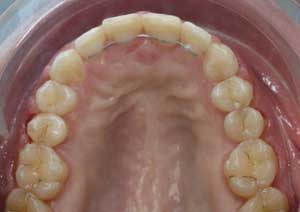

Après